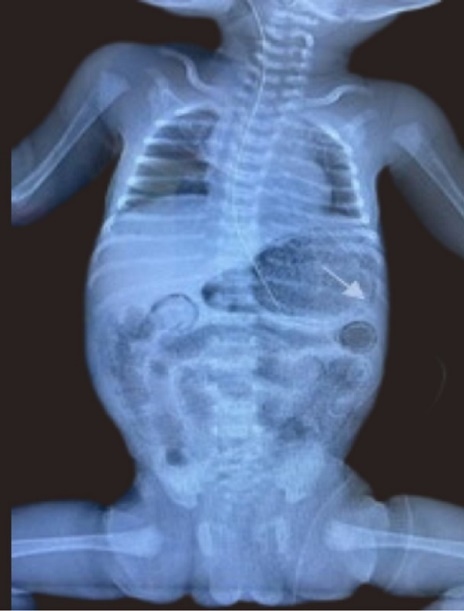

A late preterm (34+2) female infant, twin 2 of a diamniotic dichorionic gestation was delivered to a 23 year old multiparous female with minimal antenatal care, and unremarkable booking parameters. She presented with PPPROM with breech presentation and received 1 dose of dexamethasone and 2 doses of Ampicillin, one of which was administered during the intrapartum period. The baby was delivered via SVD and was suctioned and stimulated at birth. She had a birth weight of 2.11 kg. APGARs were 8 and 9 at 1 and 5 minutes respectively. Subsequent to essential newborn care, she was admitted to the NICU, screened to include blood and urine culture, complete blood count (CBC), and CXRAY and commenced on first line antibiotics. Feeds were commenced at target for age using a cow’s milk protein based formula as breast milk was unavailable. By day three of life baby was noted to have temperature instability, poor feeding, with a markedly distended firm full abdomen, with visible bowel loops. Frank blood was also noted via the nasogastric tube; however she remained haemodynamically stable. She was therefore re-screened, stepped up to second line antibiotics and an urgent A-Xray was done as shown in Figure 3. This revealed gastric pneumatosis, which was promptly recognized given the recent ‘findings of the previous case’, and pneumatosis intestinalis of small bowel. Nil portal venous gas was seen. Thromocytopenia was also confirmed; with the lowest platelet count of 93 x 103/uL(x 109/L) being observed. She was transfused with whole blood as the hemoglobin dropped from 18.0 g/dL to 14.3 g/dL. She remained NPO and received triple therapy for 14 days. Thrombocytopenia resolved. All cultures done were sterile. She recommenced feeds on Day 18 of life, subsequent to a repeat A-XRAY which confirmed radiological resolution of NEC. She subsequently had an uncomplicated outcome and was notably thriving when reviewed one month post discharge.

Figure 3.Anterior posterior Chest and abdominal radiograph showing gastric pneumatosis (arrow shown) and pneumatosis intestinalis.